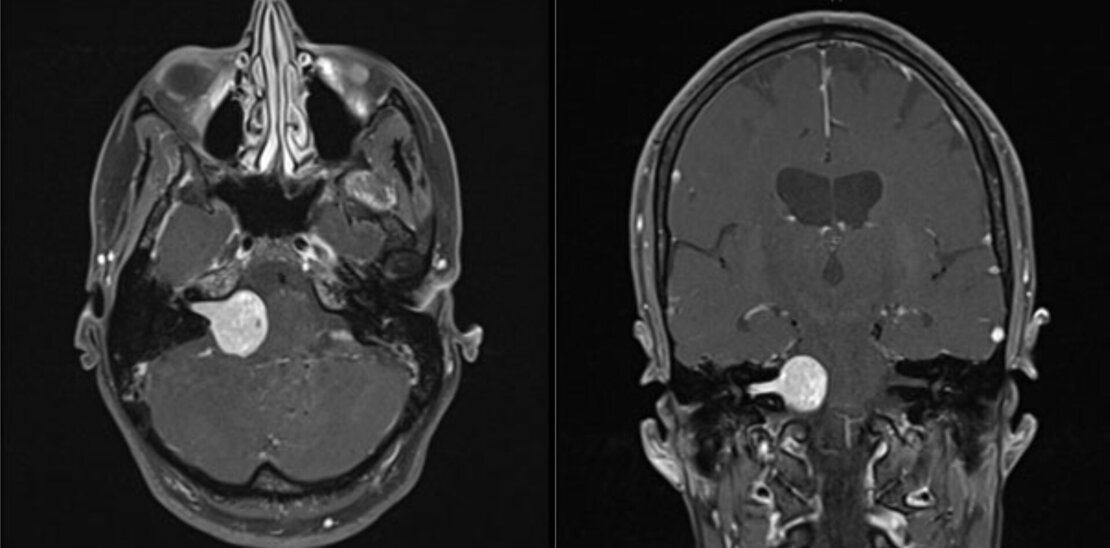

Vestibularisschwannome (Akustikusneurinome)

Diese gutartigen Tumore bilden sich aus den Hüllzellen des für das Gleichgewicht zuständigen Teils des VIII. Hirnnerven (Nervus vestibulocochlearis). Da dieser Nerv auch für die Übertragung der Impulse des Hörorgans sorgt, ist eine Hörstörung der betroffenen Seite oftmals Erstsymptom und darf insbesondere nicht mit einem Hörsturz verwechselt werden. Bei weiterem Wachstum kommt es dann - wie oben beschrieben - zu Gleichgewichts- und Gangstörungen.